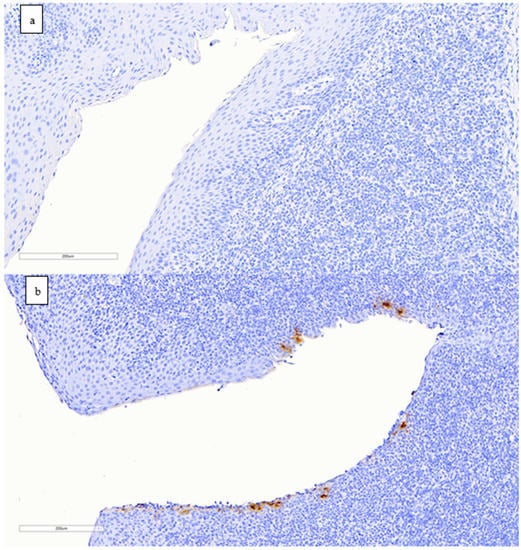

3.4. Detection of SARS-CoV-2 Nucleoprotein in Tissues by Immunohistochemistry